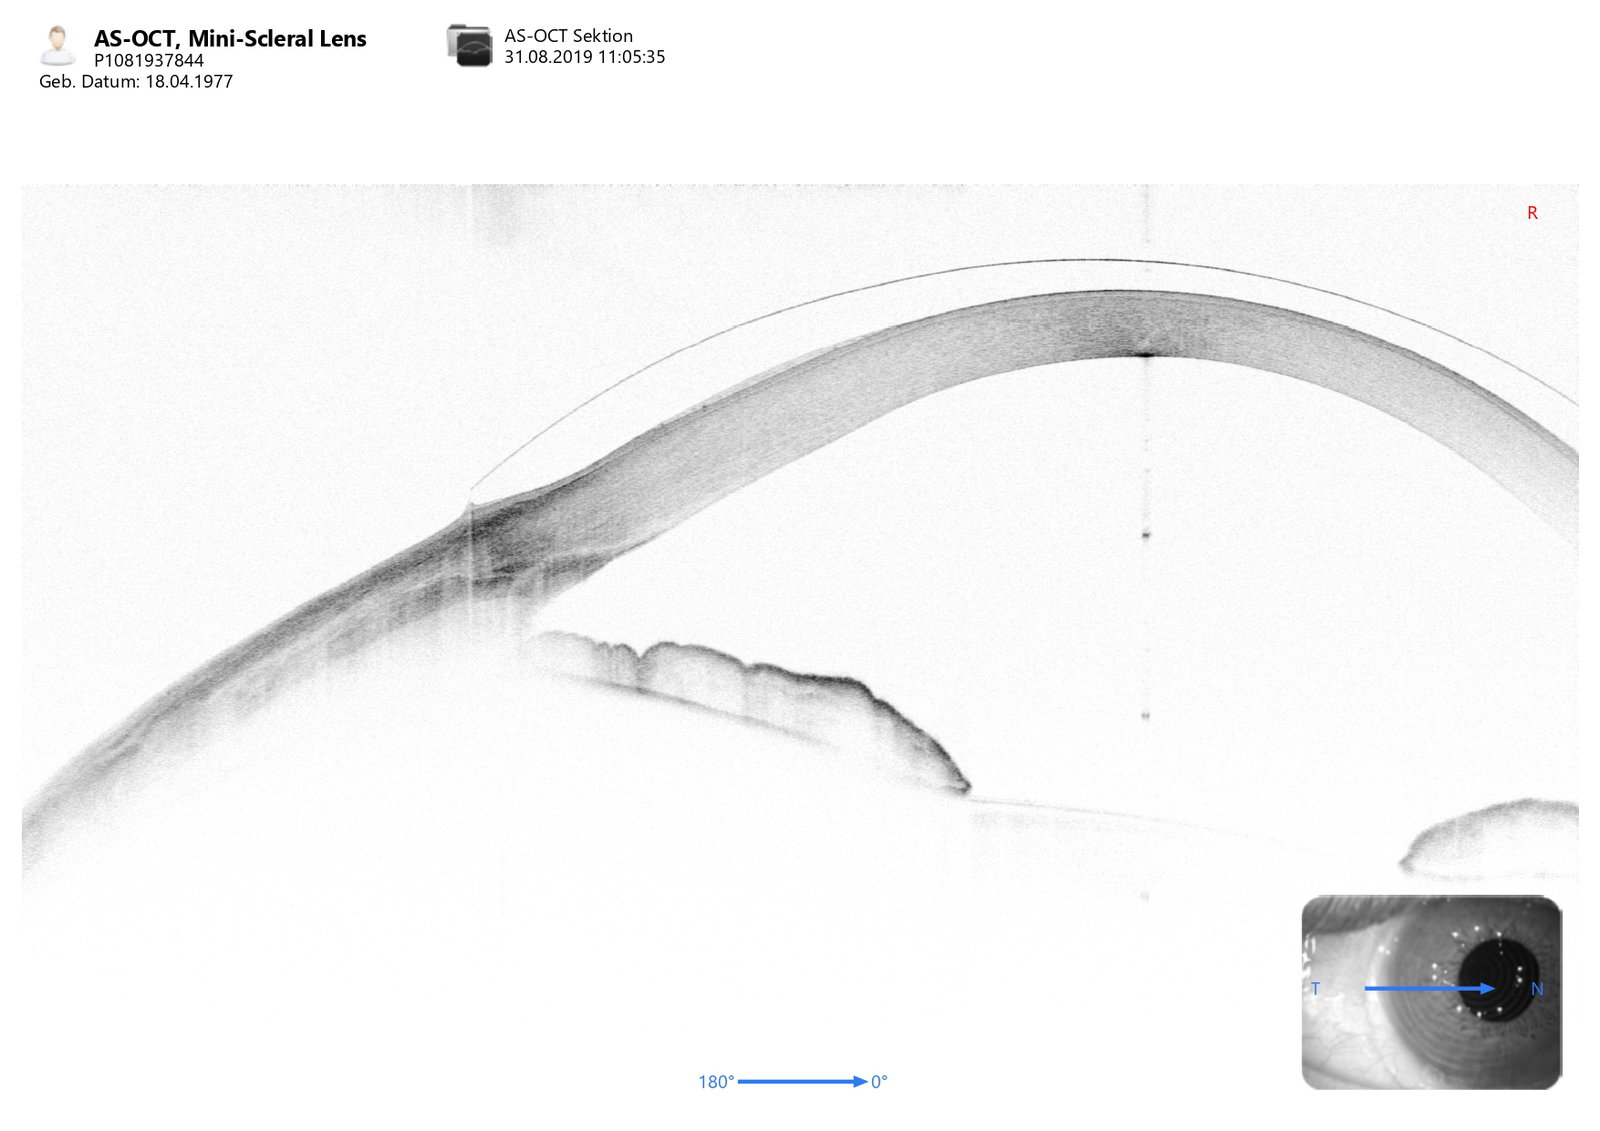

• ICL Vault kann in verschiedenen Lichtkonditionen gemessen werden

• Dank OCT-Technologie auch Mapping bei opaken Medien möglich

• Exzellente Bildqualität des vorderen Augenabschnitts über einen Durchmesser von bis zu 16 mm